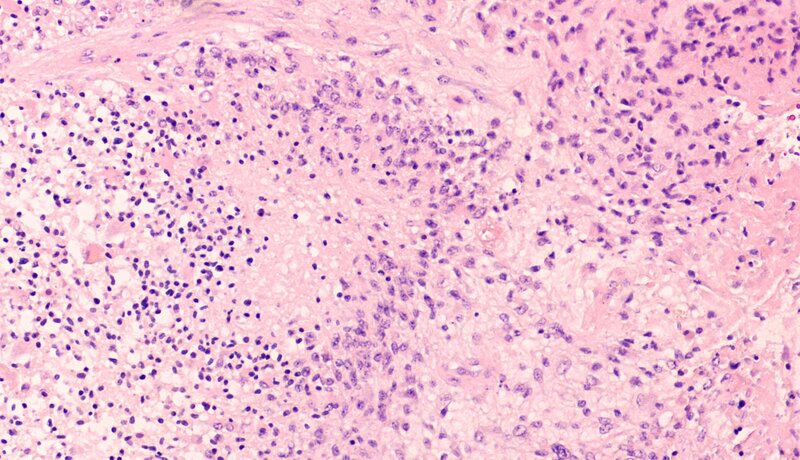

Am Glioblastom erkranken allein in Deutschland jährlich 3.000 bis 4.000 Menschen. Durchschnittlich überleben die Patienten nach Diagnose nur etwa 15 Monate. Die Zellen des Glioblastoms wachsen zum einen hoch aggressiv. Zum zweiten bleiben die üblichen Waffen der Medizin im Kampf gegen den Krebs weitgehend stumpf. Eine operative Entfernung des Tumors ist nur unvollständig möglich. Auch Chemo- und Strahlentherapie wirken nur begrenzt.

„Deshalb sucht die Medizin dringend neue Therapieoptionen“, sagt Dr. Roland Kälin. Er leitet die „neurovaskulären Projekte“ in der Neurochirurgischen Forschung. Vor mittlerweile vielen Jahren entdeckten Wissenschaftler den VEGF-Signalweg, den Krebszellen für neues Gefäßwachstum (Angiogenese) brauchen. Doch die Blockade dieses Signalweges mittels Avastin brachte keine entscheidenden Überlebensvorteile für die Patienten. Speziell in Glioblastomen kann alles sogar noch schlimmer werden: In vielen Fällen erhöht sich die Streuung von Zellen aus den Tumorherden in andere Gehirnareale noch, wodurch neue Krebsinseln entstehen. Und: Die Tumoren aktivieren alternative molekulare Signalwege für das Gefäßwachstum.

Die Münchner Forscher um Rainer Glaß haben zum Beispiel den Signalweg um den „Apelin-Rezeptor“ im Fokus. Bindet das Molekül Apelin an den Rezeptor, kommt Angiogenese in Gang. In neuen Studien mit Mäusen haben Glaß, Kälin und ihre Kollegen nun gezeigt: Ein Apelin-F13A genanntes Mini-Protein (Peptid) kann den Rezeptor besetzen, sodass Apelin nicht mehr daran binden kann. „Der Angiogenese-Signalweg ist damit unterbrochen“, erklärt Kälin. Behandelt man die Mäuse gleichzeitig mit Avastin, ist auch der VEGF-Signalweg gehemmt. Aber, ganz entscheidend: ohne dass Glioblastom-Zellen andere Hirnbereiche besiedeln. Ergebnis letztendlich: Die Lebenszeit der Nager erhöhte sich deutlich.